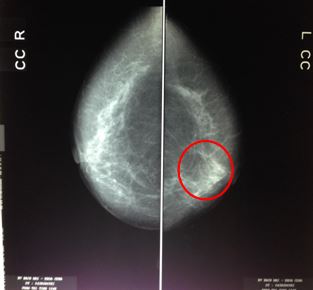

Trên phim chụp X- quang tuyến vú (mammography) cho thấy: vị trí ¼ trên ngoài vú trái có đám vi vôi hóa có tính chất ác tính (BIRADS 5). Vôi hóa lành tính vú phải.

Hình 1. Hình ảnh vi vôi hóa vị trí ¼ trên ngoài vú trái (vòng tròn đỏ)trên phim chụp X quang tuyến vú